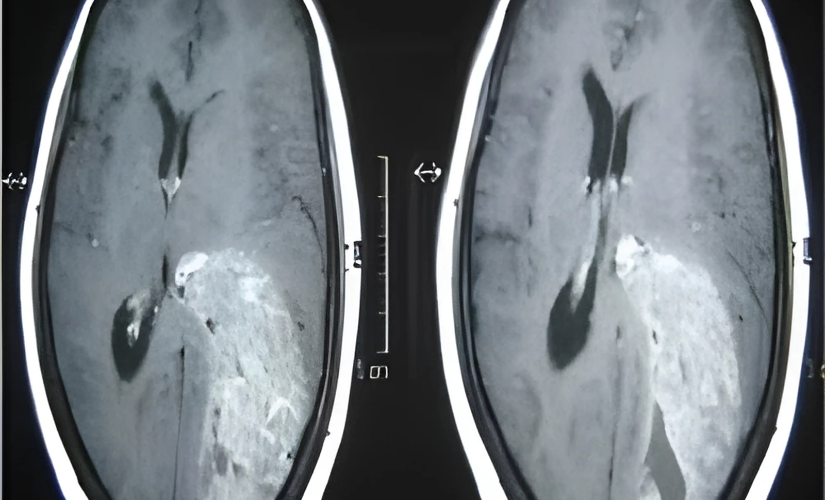

Treatment typically begins with surgical excision of the tumor, aiming for maximal removal while minimizing damage to healthy brain tissue. Advanced techniques, such as fluorescence-guided surgery, enable more precise excision. Post-surgical imaging (CT/MRI) confirms the removal. Patients then receive radiotherapy and chemotherapy to target any remaining cancer cells. Follow-up imaging helps monitor recurrence, and a clear MRI one year post-treatment, as in this referenced patient case, indicates effective management and an encouraging prognosis